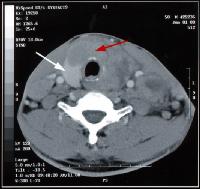

Een CT-scan van het abdomen of het kleine bekken worddt genomen om

eventuele problemen ter hoogte van de darmen, lever, nieren, milt,

enz... te beoordelen.